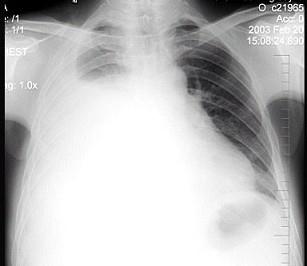

问题 男性患者,38岁,感胸闷气逼2周,近来加剧,不发热。X线检查如图,最佳诊断是 ( )

选项 A.右侧肺不张 B.右侧胸膜肥厚 C.右侧大量胸腔积液 D.右侧中量胸腔积液 E.支气管扩张

答案 C